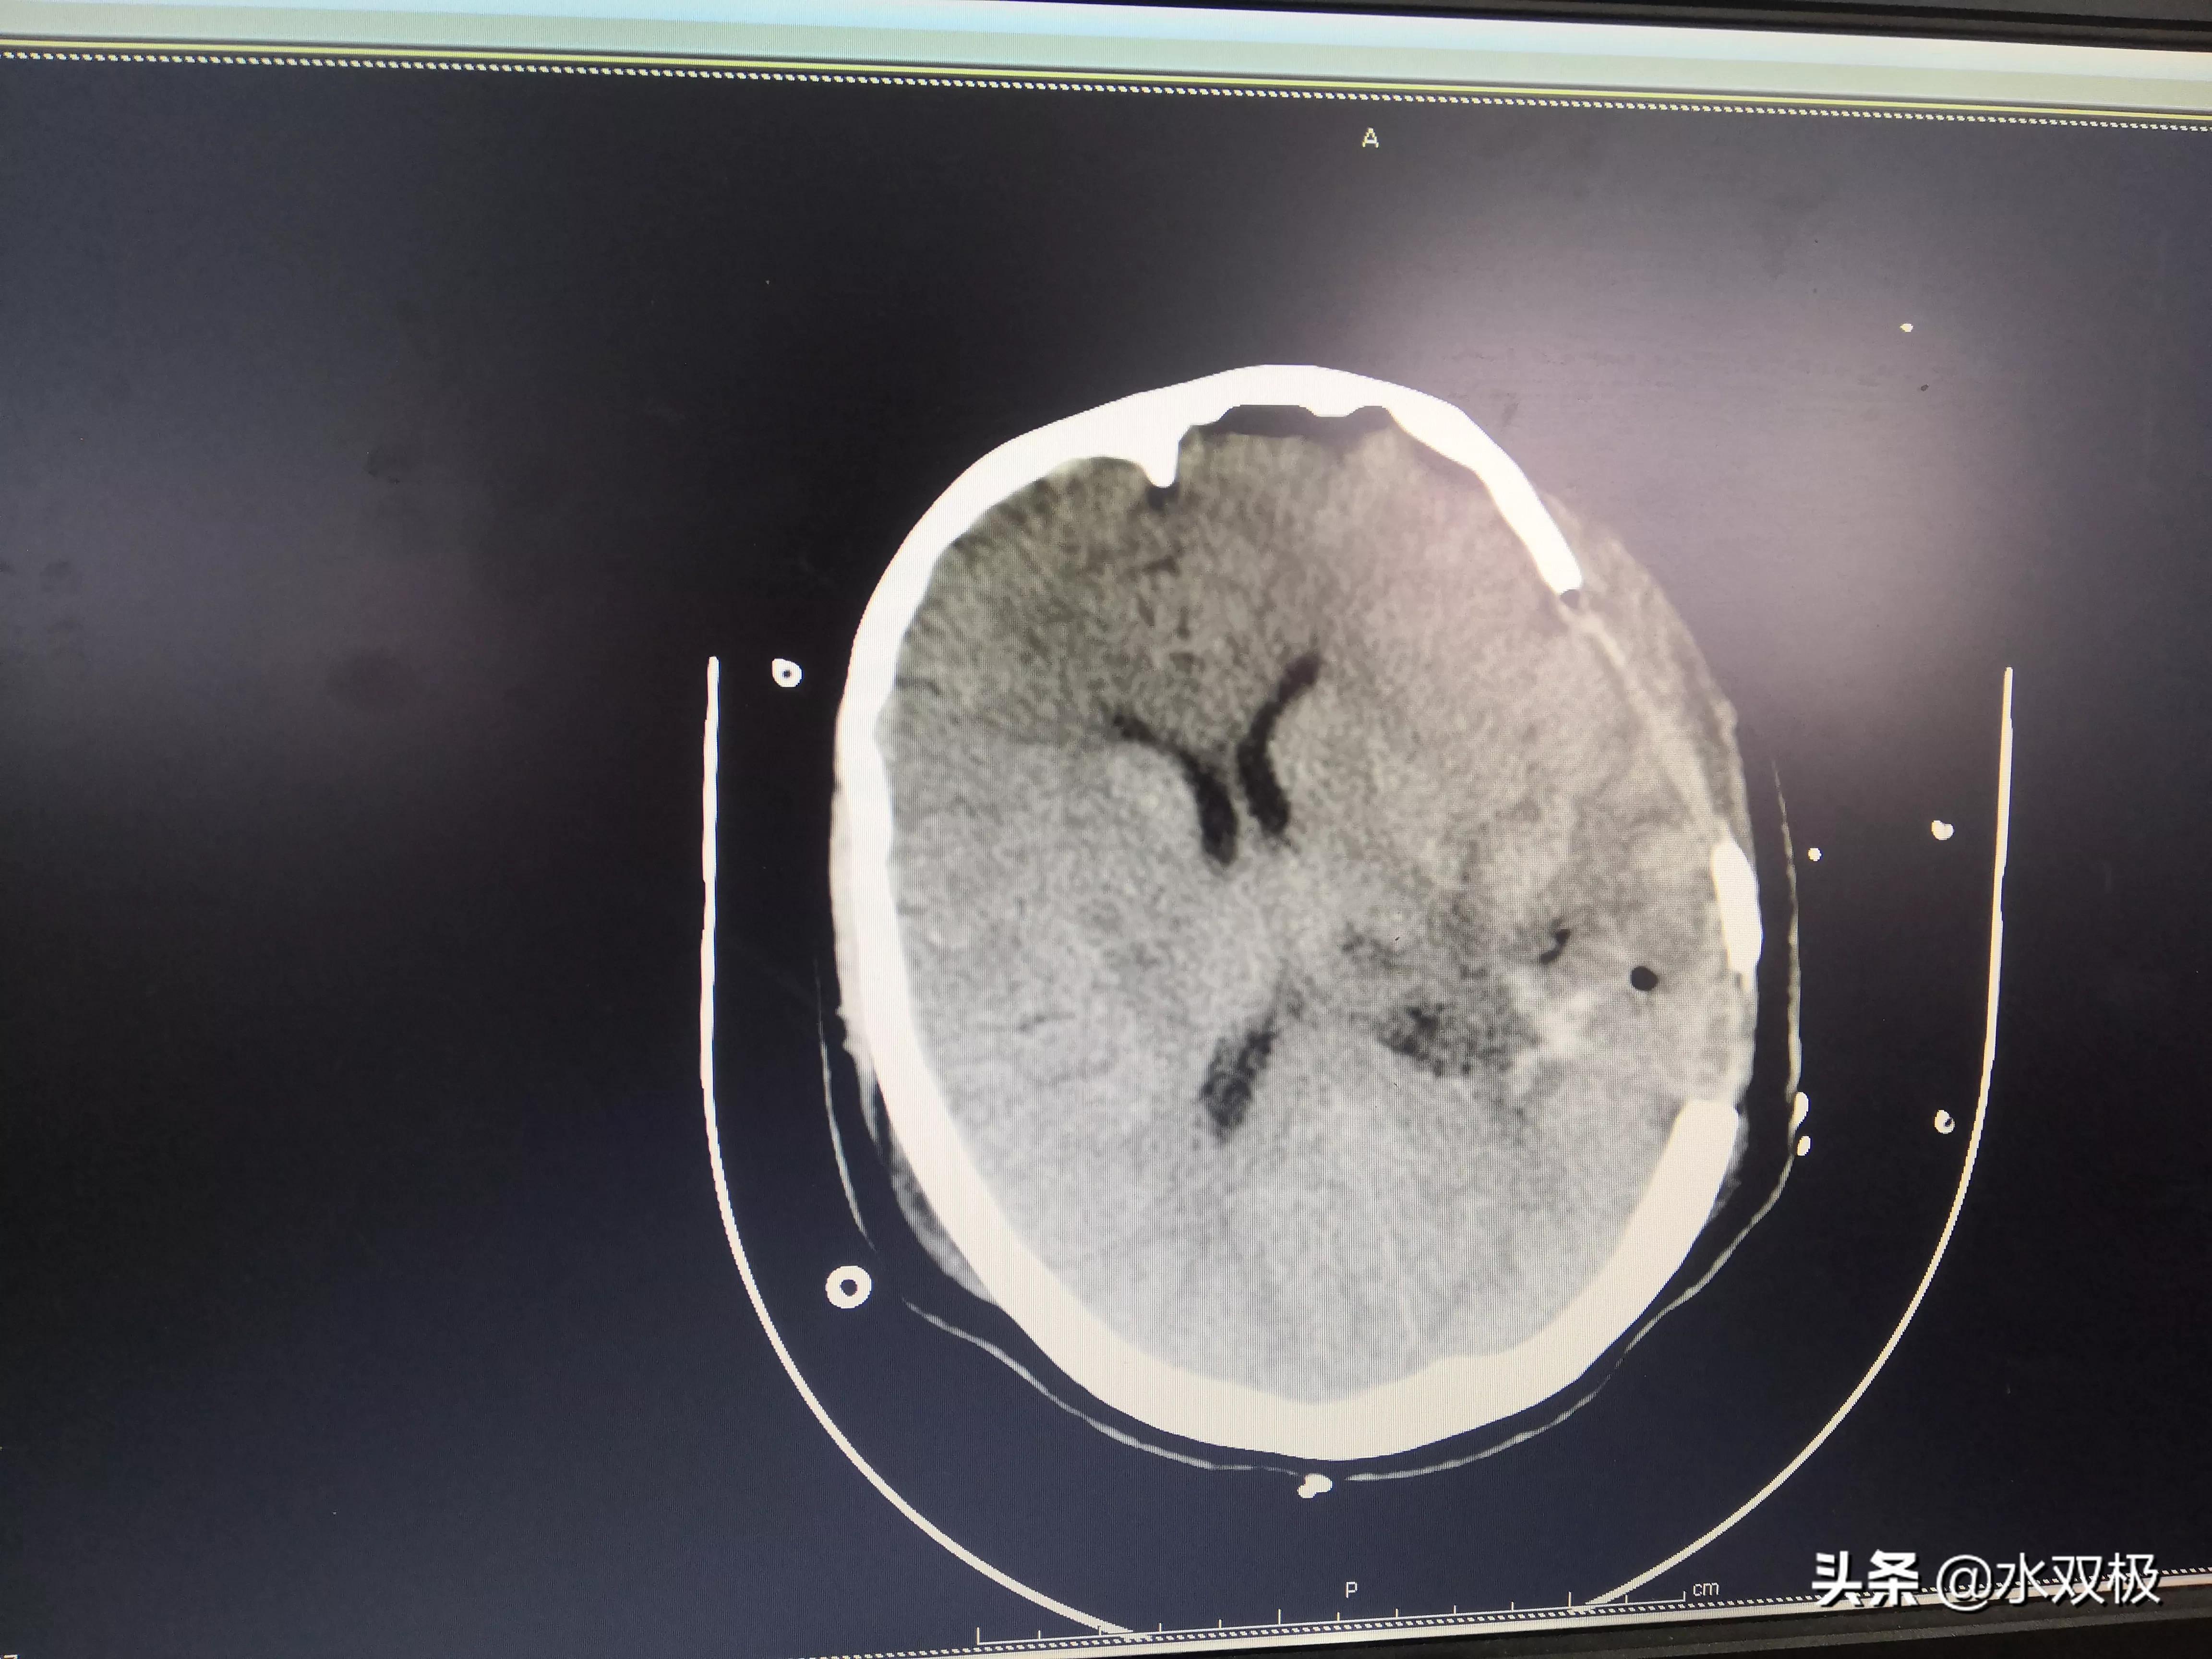

开颅血肿清除术(脑出血开颅血肿清除)

重型颅脑损伤双侧去骨瓣减压血肿清除一例 - 脑医汇 - 神外资讯 - 神